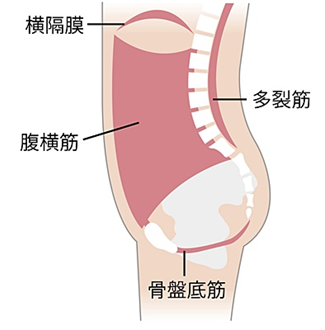

腹圧を調整する

骨盤底筋には、腹圧を一定に調整する役割もあります。腹圧とは、おなかの中の空間を保つ圧力のこと。骨盤底筋は、肺呼吸に関わる横隔膜、おなかの腹横筋、背中の多裂筋とともに腹圧を調整しており、体幹を構成するインナーマッスルとも呼ばれます。

腹圧が低下して体幹が不安定になり、姿勢が悪くなったり、内臓の働きが悪くなったりすることがあります。